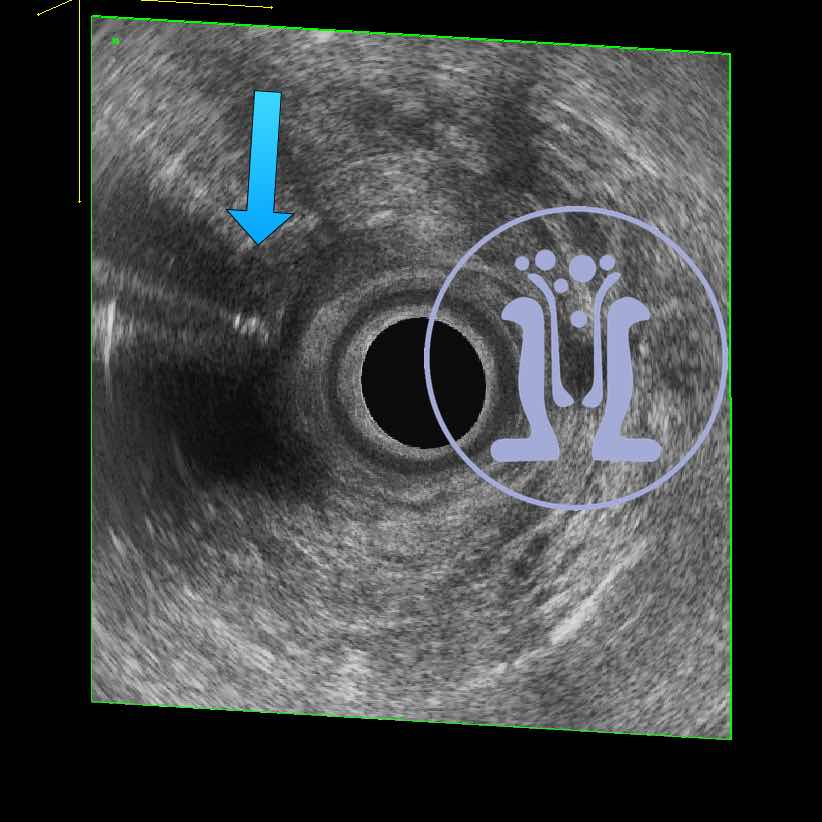

54 ετών κύριος αναφέρει εκροή πύου και φλεγμονής στη περίπρωκτικη περιοχη από 5 μήνες. Κλινικά ανευρέθηκε δερματικό στόμιο στην 3η ώρα. Στη δακτυλική εξέταση ανευρέθηκε ευμέγεθες στόμιο στην 6 ώρα. Με τη σκιαγράφηση του συριγγίου, το ενδοπρωκτικό υπερηχογράφημα επιβεβαιωσε την θέση του πρωκτικού στομίου και ταυτόχρονα έδειξε υψηλό συρίγγιο στην 6η ώρα με επέκταση έως 5 cm από το δακτύλιο του πρωκτού πίσω από την λήκυθο του ορθού.